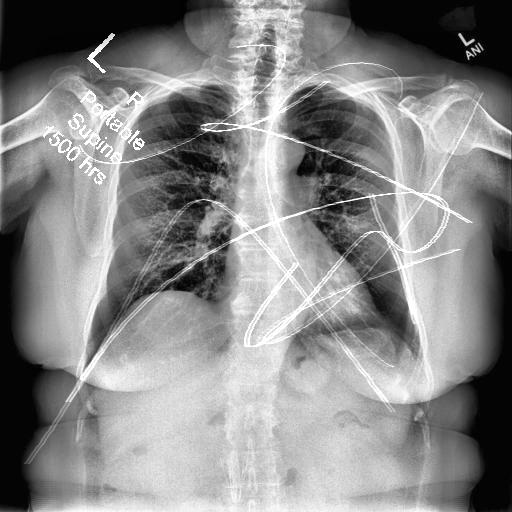

Automated catheter detection is a challenging task. Although most catheters have a radiopaque strip to facilitate detection, the strip may become less apparent depending on the projection angle. Catheters maybe confused by other similar linear structures like ECG leads and anatomy including ribs. Additionally, portions of catheters can be occluded by anatomical structures given that radiographs are a 2D projection of a 3D structure. For example, when a NGT is placed within the oesophagus, the catheter itself becomes less apparent due to the high density of the adjacent vertebrae. Finally, the number and type of catheters that could possibly appear in pediatric X-rays are unknown a priori. The catheters may be intertwined with each other thus making simple line tracing methods fail. Figure 1 gives three sample pediatric X-ray images with some common catheters highlighted in different colors.

To alleviate this annotation problem in catheter detection, we proposed to use X-ray images with simulated catheters by exploiting the fact that catheters are essentially tubular objects with various cross sectional profiles. To be more specific, a synthetic 2D projection of a catheter is generated by first simulating a horizontal catheter profile and then using it as a brush tip to draw along a B-spline path. This generated catheter is then composited with an X-ray image serving as the training data. Another contribution of this work is a segmentation network that can inherently take into account multi-scale information. This network adopts a UNet-style form and contains a recurrent module that can process inputs with increasing scales111Our code is available at https://github.com/xinario/catheter_detection.git.. We have empirically shown that by iterating through the scale space of the input image, higher recall is achieved as compared to using a single scale. Details about the methods are discussed in Section 3. Three sample detection results are shown in Figure 1.

The test dataset is collected locally and only contains frontal chest-abdominal X-rays from patients < 4 weeks old. This is the most common radiograph obtained to confirm placement of catheters such as UACs and UVCs in neonates. Currently, the test set has 35 fully labeled images with different catheter types with sample images previously shown in Figure 1. All the annotated catheters (lines excluding ECG leads) are treated as the same class in the detection.